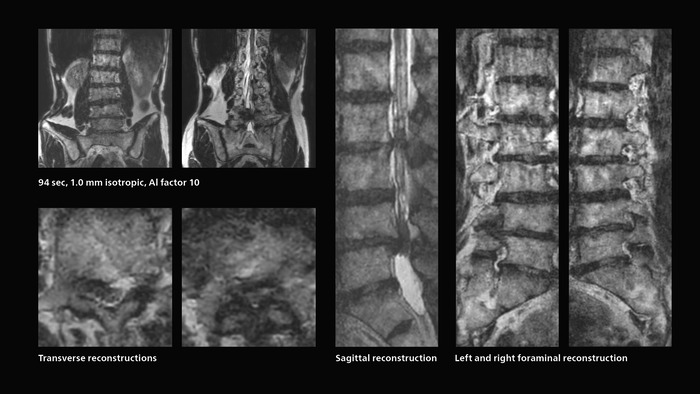

Fast lumbar spine imaging for successful exam of patient in pain

A patient arrived saying that undergoing MRI was not possible because of severe back pain and leg pain, was imaged with SmartSpeed in only 94 seconds. The scan was diagnostic and afterwards the patient confirmed that it only took a little while. Performed on Elition X.

Fast lumbar spine MRI with SmartSpeed of a patient in pain produced a successful isotropic diagnostic scan in only 94 minutes.

The hospital’s fast lumbar spine ExamCard includes T2W SpineVIEW, 1:40 min, 1.0 mm isotropic, acceleration factor 12.